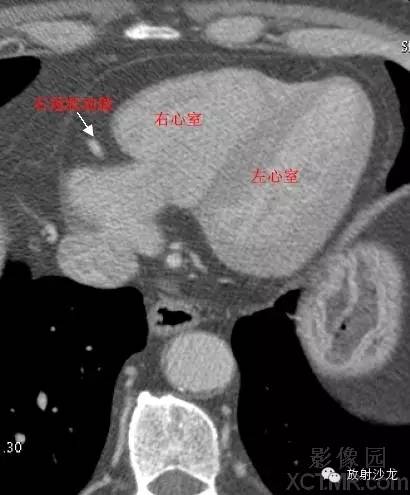

RA -Right Atrium右心房

LV -Left Ventricle左心室

RV -Right Ventricle右心室

ConusBranch右动脉圆锥支